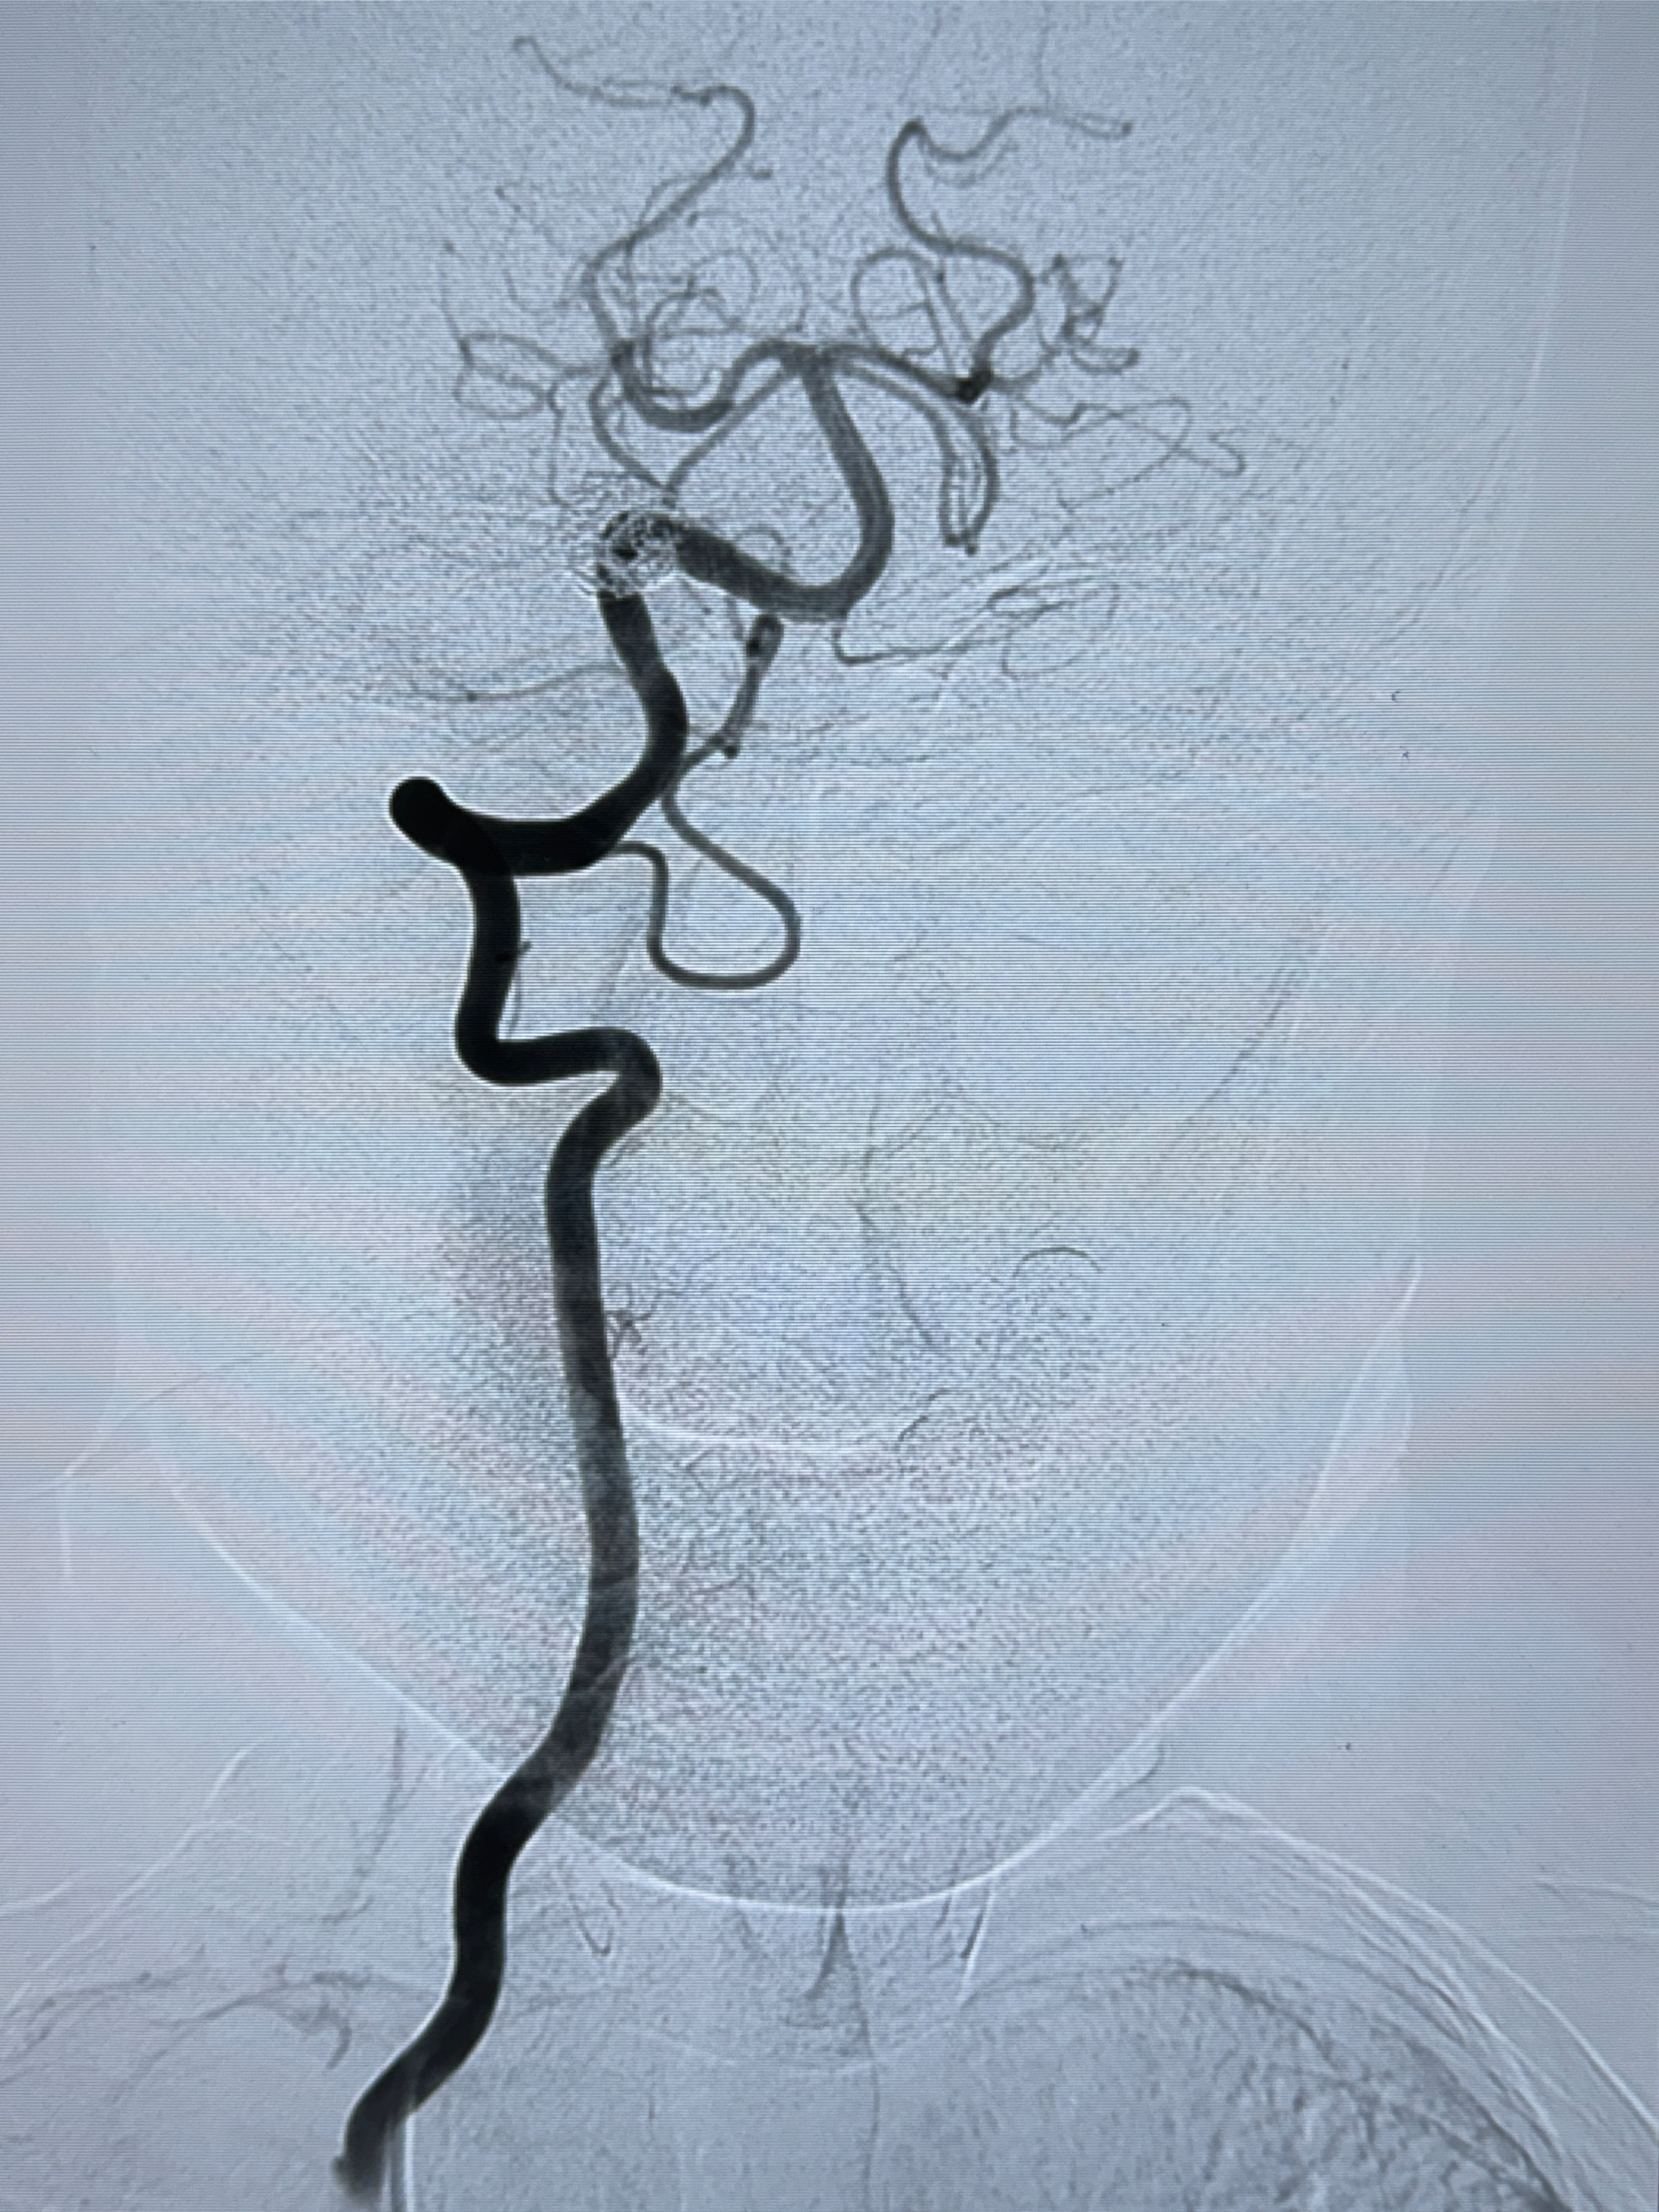

2024-01-08DSA:右侧椎动脉V4段夹层动脉瘤双支架辅助弹簧圈栓塞术后

患者支架辅助治疗后18个月,动脉瘤痊愈